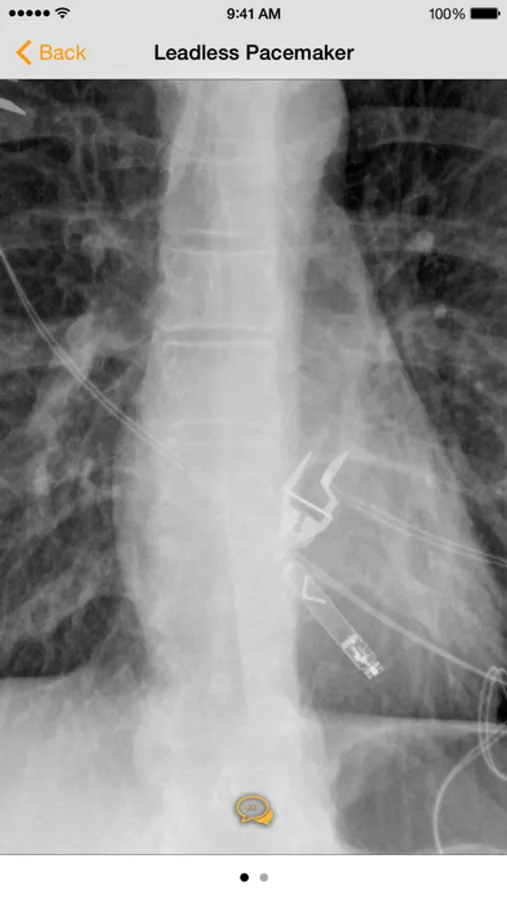

· Countless images, organized into the following categories: Common Cardiac Conduction Devices, Less Common Cardiac Conduction Devices, Vascular Devices, Airway Devices, Enteric Devices, Neurological Devices, Musculoskeletal Devices, and Miscellanenous Devices.

· Tap the caption icon to read more about the device and to see it highlighted on the chest radiograph.